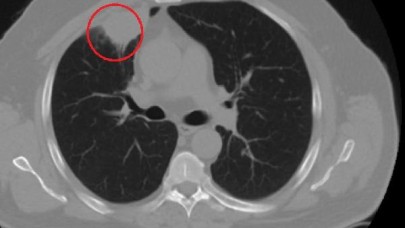

Dünyada bir ilk Türkiye'de yaşandı: COVID-19, akciğer kanserini taklit etti!